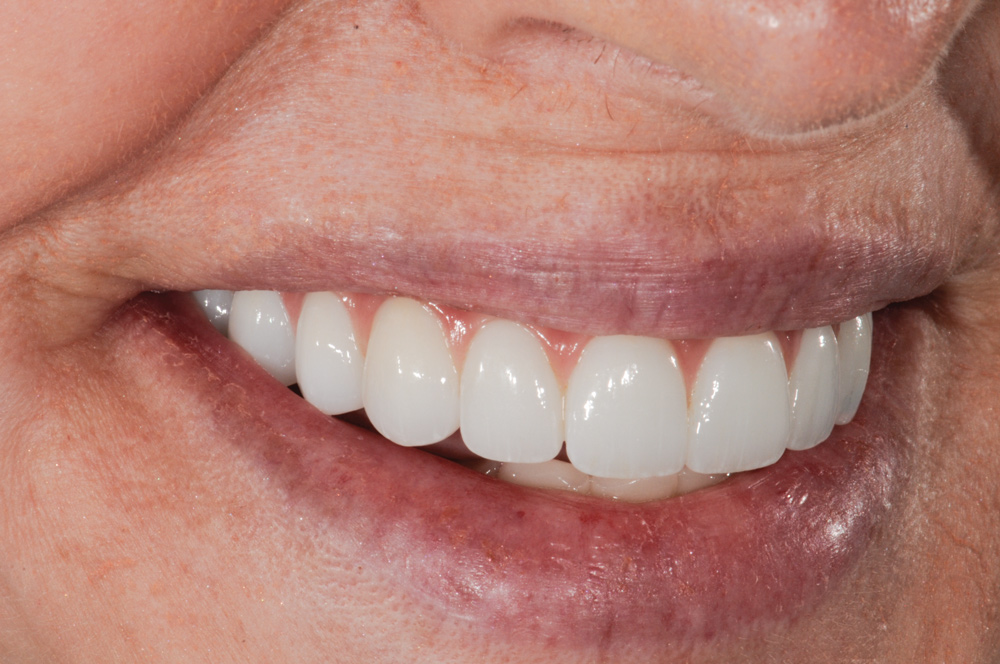

Full-monolithic zirconia is more difficult to make natural and lifelike but is definitely possible to do (Figure 17). Having a clear vision of the outcome and spending adequate time in the green stage shaping and creating definition while preserving the strength of the material is necessary. Some effects can be done after sintering using 3D stains specifically for this purpose. These stains create a silky finish and enhance the effects.

Minimally layered and full-monolithic zirconia can be hard to detect when these methods are followed. Full-monolithic zirconia looks as good as layered, is less costly to the patient and dentist, is stronger, and will not chip (Figure 18). The philosophy at the author’s laboratory is to devote more time in the green stage to maximize the illusion of reality to create natural-looking full-monolithic restorations.

Fig 5. Beautiful, natural esthetics that mimic nature with monolithic solid zirconia with layered pink ceramic for the best success.

Figure 5

Fig 18. Full-monolithic zirconia prosthesis looks as good as natural teeth and layered ceramic.

Figure 18

Fig 19. Patient’s smile with monolithic solid zirconia prosthesis (no cutback for porcelain).

Figure 19